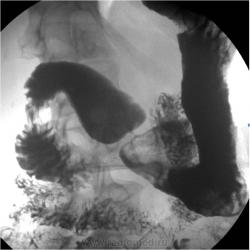

Здравствуйте Виктор Григорьевич, я так понимаю в н/3 тела желудка, по малой кривизне, язвенная ниша(красные стрелки), а вот ниже угол желудка сглажен складывается впечатление об оттеснении из вне(отмечено синими стрелками).

Такое оттеснение можно получить и искусственно, применив "мягкий дистинктер". А, вот "язвенная ниша" довольно скверная. На мой взгляд, не столько "ниша", сколько изъязвление.

Снимки - в положении лёжа? Уж, не на животе-ли?

Ничего то от Вас, Виталий, не скроешь....да - язва желудка, да - киста тела поджелудочной железы....

Снимки:первый - стоя; второй - лежа на спине, мягких компресионных приспособлений не применяю.

А первый (тот что слева) не может быть стоя. Физика против: в своде желудка барий, а в антральном отд. воздух. Лёжа на левом боку (правое косое).